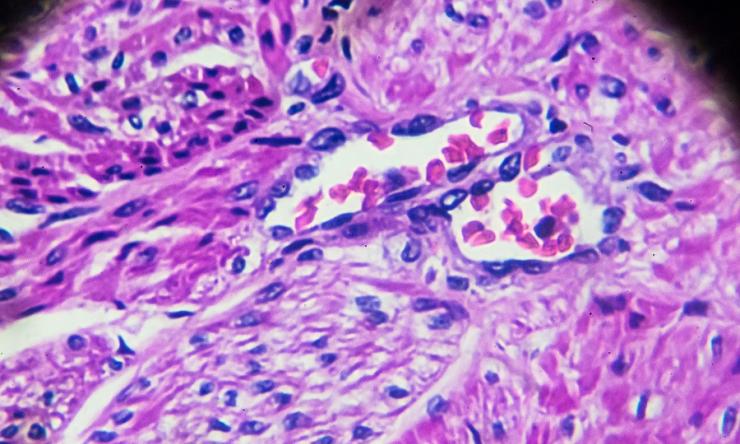

Adenocarcinoma of the endometrium: Cancer that develops in the glands lining the uterus, known as the endometrium; more than 95 percent of uterine cancers are endometrial cancer

Endometrial uterine cancers are sometimes preceded by pre-cancerous lesions called hyperplasia. Hyperplasia is an overdevelopment of the endometrial glands that can turn into cancer but is not cancer. It can range from “simple” (further away from cancer) to “complex” (closer to cancer) and with or without atypia, which is a precancerous change.